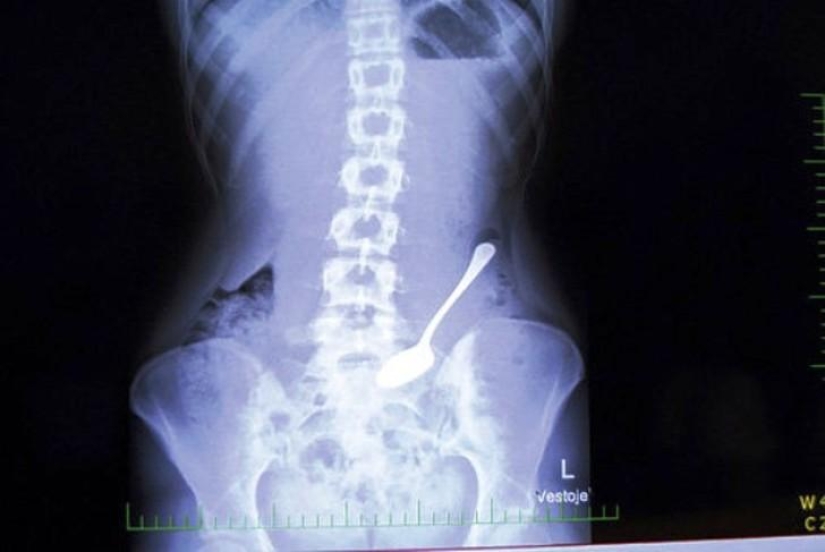

Spoon.